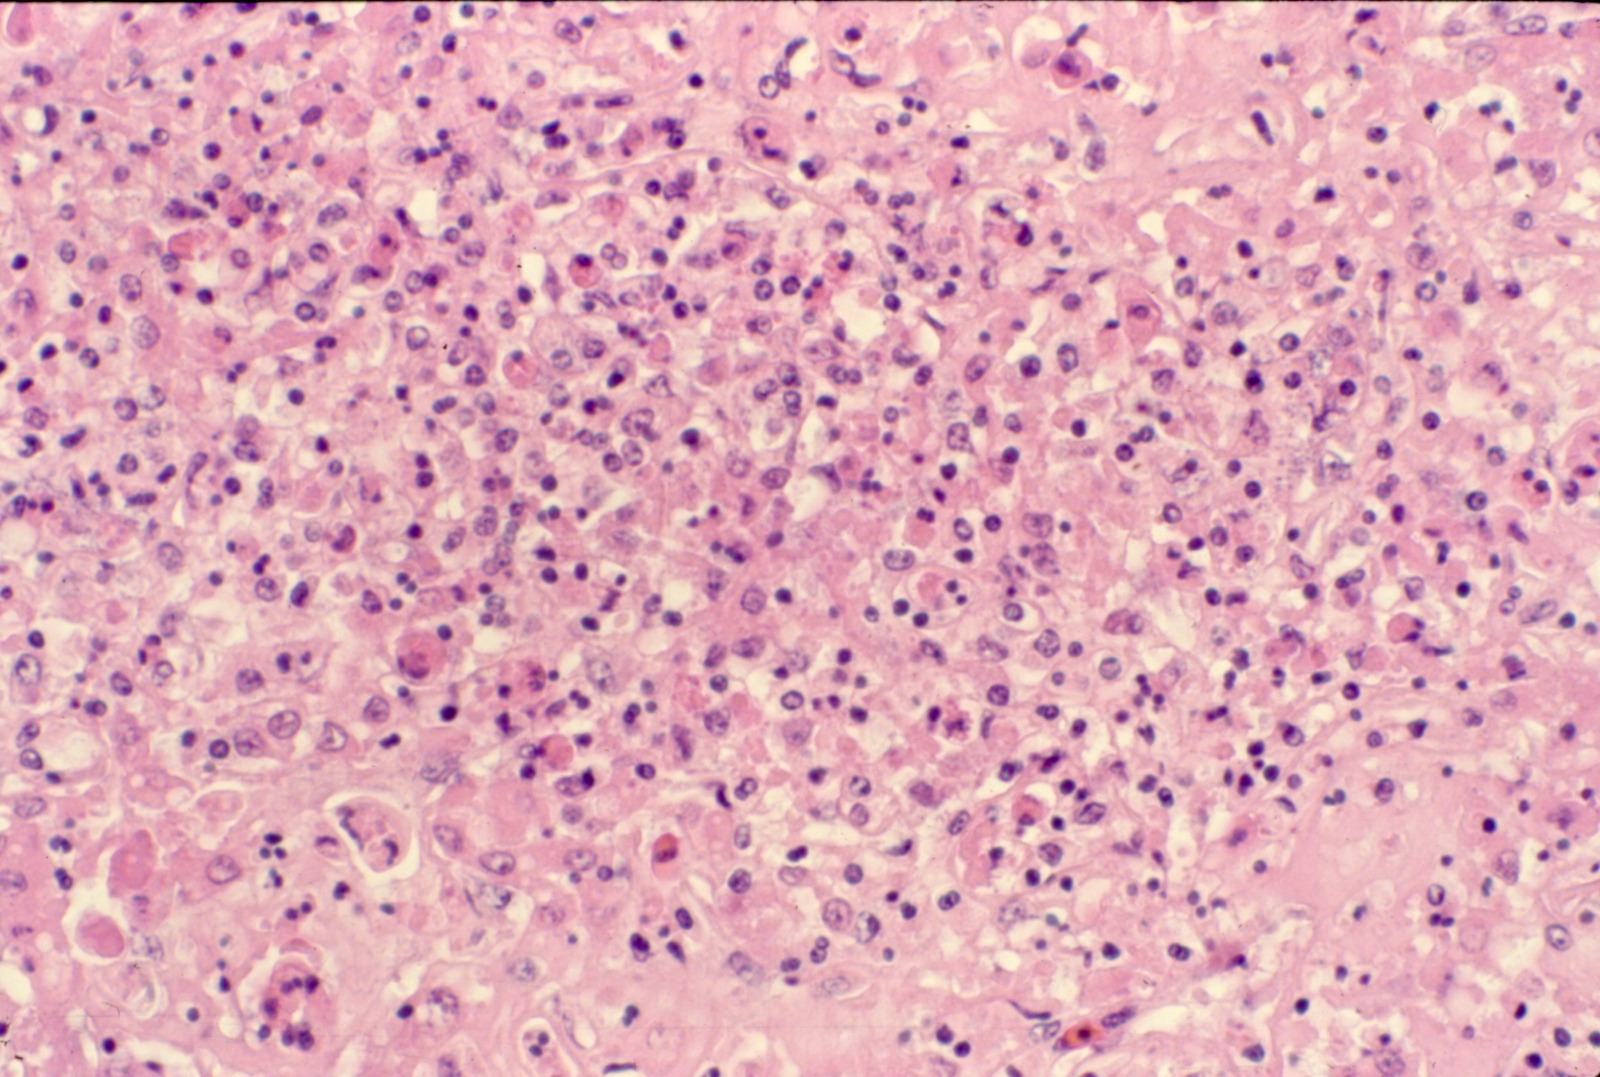

Fowl cholera (slide study set no. 19) Item Info

Fowl cholera (slide study set no. 19)

Poultry--Diseases Chicken cholera

Slide Study Set #19, Fowl Cholera (includes 25 color slides), undated